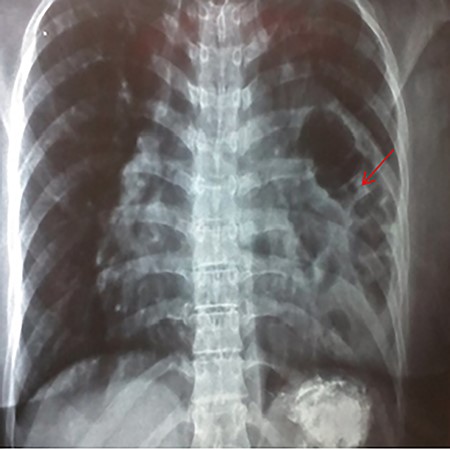

A 35-year-old primigravida female patient complained of mild chest and epigastric pain. Twenty months earlier, she underwent a successful emergent caesarian surgery for preeclampsia, which was performed without complication. Since then, the patient complained of an episodic spasmo-colic pain in the left chest and abdomen that radiated to the left scapula and the upper back. On current presentation, she reported dyspnea and palpitation with sub-sternal heaviness. These symptoms were accompanied by a dry cough, orthopnea and palpitations. No change in bowel movements or any other complaints were reported or evident. She reported no history of surgery except for the cesarean section, which was uncomplicated. She reported no previous trauma, her family history was insignificant and the physical examination was normal. Pfannenstiel incision scar was well-healed with no erythema or drainage, and no tenderness or palpable masses were present around the scar or underneath it. Chest X-ray (Fig. 1) showed an enlarged cardiac silhouette, a closed left costo-diaphragmatic angle and an opacity that covered the left lower border of the heart and the left diaphragmatic dome. The right hemi-thorax was normal. Pleural effusion was suspected and thoracentesis was conducted. The drained fluid labs showed a neutrophilic exudative bloody liquid. Following this, a barium swallow (Fig. 2) was performed, which showed abdominal viscera to be herniated into the thoracic cavity with no other abnormalities. Chest and abdomen computed tomography (CT) scan with contrast (Fig. 3) showed a non-homogeneous opacity in the left side of the thoracic cavity that pushed the heart and other mediastinal components to the right. It was compatible with herniated abdominal viscera, suspected to be either a Morgagni hernia or as a result of a neglected trauma to the diaphragm (although the patient denied any trauma). Surgery was indicated using the thoracic approach. Under general anesthesia, the left chest was entered through the sixth intercostal space, and the thoracic cavity was found to be normal with no signs of hernia. The pericardium was opened and explored; the great omentum and colon were found to be protruded through the diaphragm into the pericardial sac. A defect of 5 cm in diameter was found in the central tendon of the diaphragm (Fig. 4). The adhesions between the pericardium, myocardium and the viscera were released. The viscera were then reduced back into the abdominal cavity through the hernia. The hernia was primarily sewed with running proline suture then covered with 5 × 5 cm proline patch which was supported with a pericardium patch. Finally, the pericardium was partially closed. Three days later, the chest drain tube was removed and the patient discharged in good status. A 2-week follow-up chest X-ray showed no abnormalities and monthly chest X-rays were indicated for a year, and were all normal.

CXR showing an abnormal heart index and opacity that covers the left pleural angle.